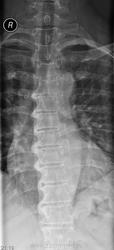

Пол пациента: Женский пол Тип патологии: Метаболическое заболевание Область исследования: Скелетно-мышечная система Методы исследования: Rg Синдесмофиты по боковой поверхности позвонков Th IV - Th11. Болезнь Форестье? https://radiomed.ru/sites/default/files/styles/case_slider_image/public/user/19785/f_t_spine_20140325_110901.jpg?itok=rvYoDwaG ID:36388 Tue, 25/03/2014 - 19:22 #1 Dima Offline Last seen: 7 years 4 months ago Joined: 05.08.2012 - 17:39 Posts: 2467 Форестье нет. Возможно болезнь Бехтерева. Терпимость - это когда прощают чужие ошибки; такт - когда не замечают их. (Артур Шницлер) Tue, 25/03/2014 - 19:49 #2 maker4ik Offline Last seen: 8 years 9 months ago Joined: 19.10.2011 - 17:49 Posts: 2682 Форестье или Бехтерева. Доснимите ИСС. Tue, 25/03/2014 - 20:16 #3 И.Бондаренко Offline Last seen: 5 days 4 hours ago Joined: 13.09.2011 - 22:55 Posts: 9208 Если в анализах СОЭ повышено, и есть сакроилеит и заращение межпозвонковых суставов (проекция в 3/4) - то скорее Бехтерева. А так Форестье. Tue, 25/03/2014 - 21:08 #4 Андрей Юрьевич Offline Last seen: 3 weeks 3 days ago Joined: 16.11.2008 - 22:16 Posts: 18101 перчик wrote: ... Болезнь Форестье?Или? Андрей Юрьевич Tue, 25/03/2014 - 21:49 #5 Dima Offline Last seen: 7 years 4 months ago Joined: 05.08.2012 - 17:39 Posts: 2467 И.Бондаренко wrote: Если в анализах СОЭ повышено, и есть сакроилеит и заращение межпозвонковых суставов (проекция в 3/4) - то скорее Бехтерева. А так Форестье. Как так? Почему форестье, связка на уровне тел не окостенелая... Терпимость - это когда прощают чужие ошибки; такт - когда не замечают их. (Артур Шницлер) Sat, 14/10/2017 - 08:44 #6 Катенёв Валенти... Offline Last seen: 7 years 2 months ago Joined: 22.03.2008 - 22:15 Posts: 54876 Dima wrote: Форестье нет. + Wed, 11/04/2018 - 16:59 #7 NataSey Offline Last seen: 7 years 10 months ago Joined: 11.04.2018 - 16:54 Posts: 2 Здравствуйте. Я перевожу мед.заключение. Помогите, пожалуйста, с расшифровкой ИСС. Речь идет о сцинтинрафии костей скелета. Огромное спасибо!!! Wed, 11/04/2018 - 17:28 #8 NIL Offline Last seen: 1 month 3 weeks ago Joined: 25.11.2013 - 20:50 Posts: 18208 NataSey wrote: Помогите, пожалуйста, с расшифровкой ИСС. ИСС= Илеосакральные сочлениения(если правильно понят вопрос) "Слушай всех, прислушивайся к немногим, решай сам".© Thu, 12/04/2018 - 08:22 #9 NataSey Offline Last seen: 7 years 10 months ago Joined: 11.04.2018 - 16:54 Posts: 2 Да.Большое спасибо Вам!!!!

Форестье нет. Возможно болезнь Бехтерева.

Форестье или Бехтерева. Доснимите ИСС.

Если в анализах СОЭ повышено, и есть сакроилеит и заращение межпозвонковых суставов (проекция в 3/4) - то скорее Бехтерева. А так Форестье.